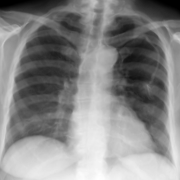

Refer to caption

(a) real

(b) μ=0.001𝜇0.001\mu=0.001

(c) μ=0.005𝜇0.005\mu=0.005

(d) μ=0.01𝜇0.01\mu=0.01

Figure 3: Chest radiographs resulting from PriCheXy-Net when using different deformation degrees μ𝜇\mu. Images were cropped to better highlight the diagnostically relevant area.

The results of our proposed PriCheXy-Net (see Table 1) show more promising behavior. As can be seen, increasing deformation degrees μ𝜇\mu lead to a successive decline in patient verification performance. Compared to the baseline, the AUC decreases to 74.7 % (μ=0.001𝜇0.001\mu=0.001), to 64.3 % (μ=0.005𝜇0.005\mu=0.005), and to 57.7 % (μ=0.01𝜇0.01\mu=0.01), indicating a positive effect on patient privacy and the obfuscation of biometric information. In addition, PriCheXy-Net hardly results in a loss of data utility, as characterized by the constantly high classification performance with a mean AUC of 80.4 % (μ=0.001𝜇0.001\mu=0.001), 79.3 % (μ=0.005𝜇0.005\mu=0.005), and 76.2 % (μ=0.01𝜇0.01\mu=0.01). These findings are further visualized in the privacy-utility trade-off plot in Fig. 2. In contrast to the examined comparison methods, the data point corresponding to our best experiment with PriCheXy-Net (green) lies near the top right corner, highlighting the capability to closely satisfy both objectives in the privacy-utility trade-off. Examples of deformed chest radiographs resulting from a trained model of PriCheXy-Net are shown in Fig. 3. More examples are given in Suppl. Fig. 1. Difference maps are provided in Suppl. Fig. 2.